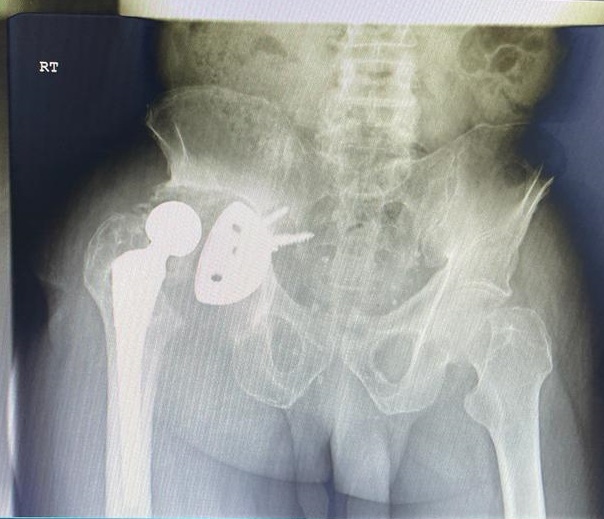

71-year old male with a right total hip following fracture dislocation 21 years ago presents with a 6 month history of increasing pain and shortening of the right lower limb. Recommended for acetabulum revision. Performed with graft multi hole revision cup and change of femoral head to 36 mm